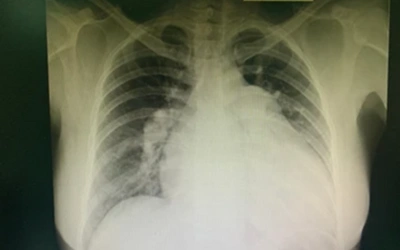

Chest X-Ray:

Helps in the identification of changes in the lung structure, such as accumulation of fluid or lung injury that may lead to PH.